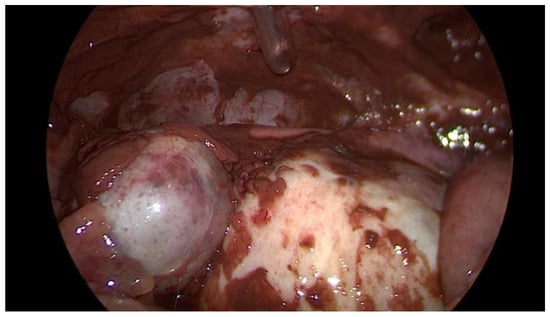

Data collection: The patients’ backgrounds, clinical symptoms at admission, sonographic and laboratory assessment, as well as intraoperative findings were recorded. Patient demographic data included age, menopausal status, presence of dysmenorrhea, history of endometriosis surgery, and use or non-use of hormonal downregulation therapy for endometriosis. Pre-operative laboratory tests included white blood cell (WBC) count, serum C-reactive protein (CRP) level, and serum CA125 level, and all patients underwent transvaginal sonography (Figure 1) on admission as part of the emergency diagnostic assessment. The maximal diameter and the location of the endometriomas were noted. The intraoperative findings included the location of the ruptured endometriomas (Figure 2 and Figure 3), the presence and classification of endometriosis according to the rASRM [16] and #ENZIAN [17] systems, and, lastly, total blood loss.

Figure 2. Intraoperative laparoscopic display of a ruptured endometrioma of the left ovary in a 43-year-old woman.